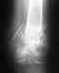

Ставят разные диагнозы: переломовывих и перелом основания средней фаланги 2-го пальца.

Т.к. перелом сросся неправильно, прошу ответить, какой диагноз более правильный. Нужен ли был остеосинтез?